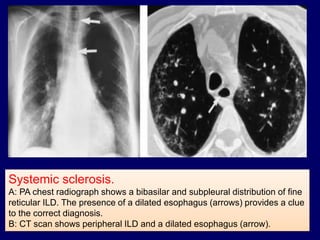

Pulmonary fibrosis and rheumatoid arthritis.

Systemic sclerosis.

A: PA chest radiograph shows a bibasilar and subpleural distribution of fine

reticular ILD. The presence of a dilated esophagus (arrows) provides a clue

to the correct diagnosis.

B: CT scan shows peripheral ILD and a dilated esophagus (arrow).

Systemic sclerosis. A: PAchest radiograph shows a bibasilar and subpleural distribution of fine reticular ILD. The presence of a dilated esophagus (arrows) provides a clue to the correct diagnosis. B: CT scan shows peripheral ILD and a dilated esophagus (arrow).